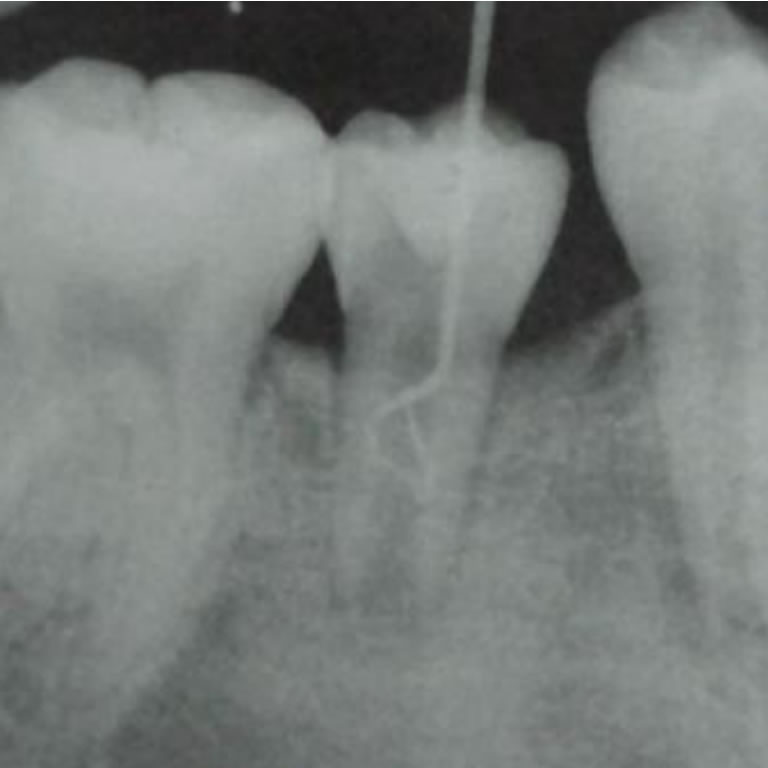

Regeneracion de Tejidos Dentario

Dra. Elena Pruskin

Los tratamientos endodónticos no quirúrgicos en dientes inmaduros infectados suelen ser exitosos, pero no regeneran los tejidos ni permiten el desarrollo normal del ápice. Así, la apexogénesis no se logra mediante estas terapias convencionales.